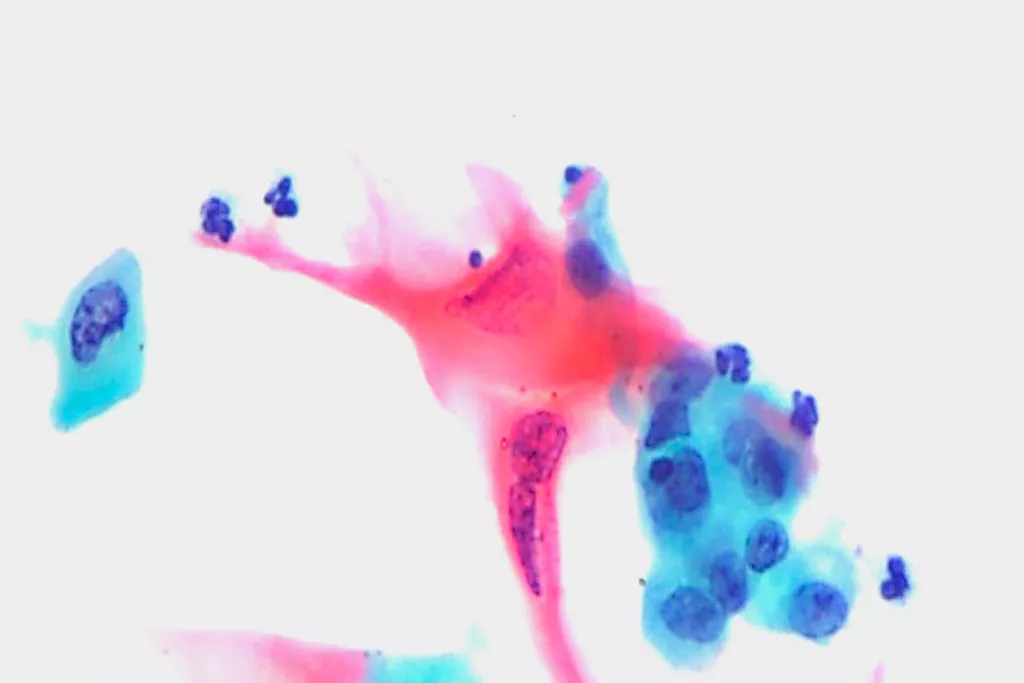

Galeria de imagens9

9. Imagens do Departamento de Citopatologia, Llandough Hospital, País de Gales